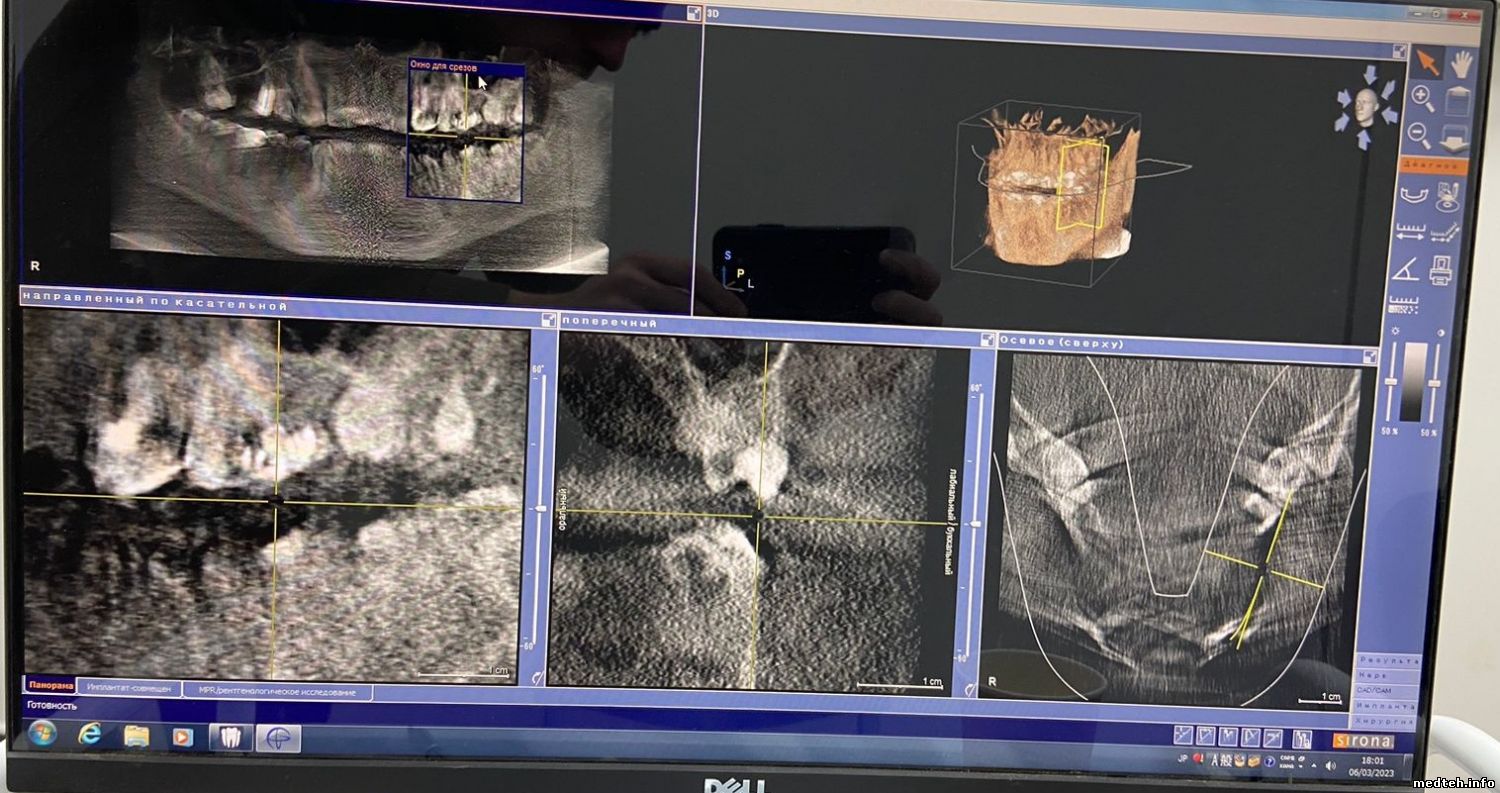

Orthophos XG 3D от Sirona. Плохое качество изображения.

Подскажите, пожалуйста, в чём может быть проблема?

Фото прилагаю:

1605363.jpg (270.0 Kb) · 6676121.jpg (173.7 Kb) · 8381895.jpg (212.7 Kb)

Фото прилагаю.

Goodboy03, по 3D снимку: проверить ошибки в логе аппарата, потом, скорее всего, калибровка. Потом по результату.

По панораме:

1. Матрицы датчика либо всё, либо датчик крепко тряхнули/ударили, что на OPXG3D сделать сложновато.

Есть вероятность, что окислы на разъёмах частей матрицы, для этого надо разбирать датчик, однако немцы это не рекомендуют;

2. Есть очень маленький шанс, что проблема в кабеле поворотного модуля датчиков.

3D снимок снят после всех калибровок, которые были прописаны в мануале. Ошибок нет.

По панораме: датчик был вскрыт после всех манипуляций, которые не повлияли на результат, окислов нет, всё как новое. Если, конечно, я правильно понял, про какой датчик Вы имели ввиду (фото прилагаю).

Подскажите ещё, пожалуйста, а то что 3D снимок получается некачественный, от датчика это уже не зависит?

Тогда в чём может быть проблема ещё и с 3D?

3866273.jpg (212.7 Kb)

Goodboy03, с 3D неоднозначно, надо проверять датчик, диафрагму, излучатель.